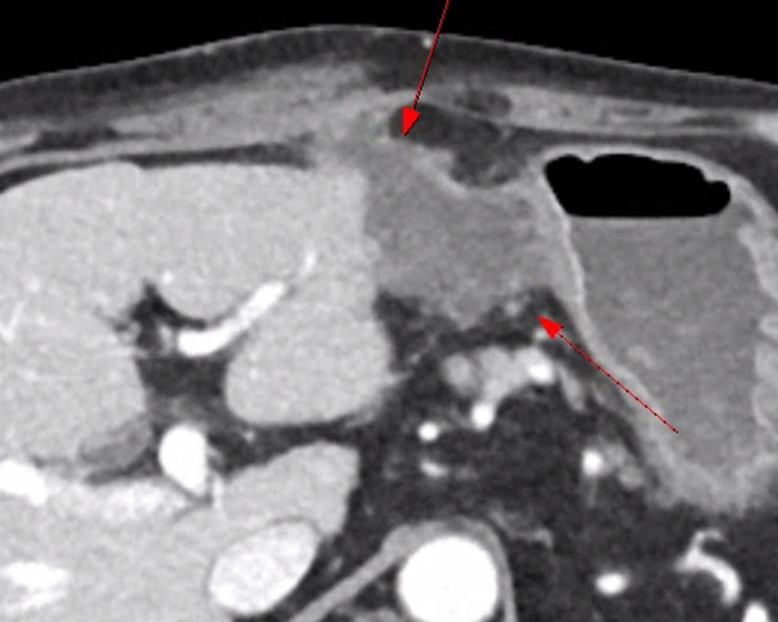

| 간 농양 (0) | 2024.03.31 |